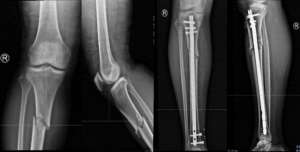

赵滨(引领骨科新纪元:髓内钉微创技术,重塑四肢骨折治疗新标准)齐鲁晚报·齐鲁壹点 陈甜田 通讯员 赵滨在骨科医学的浩瀚星空中,髓内钉技术犹如一颗璀璨的明珠,以其微创、高效、稳定的特性,为四肢骨折患者带来了福音。滨州市人民医院创伤外科在肱骨骨折、股骨粗隆间骨折、股骨粗隆...